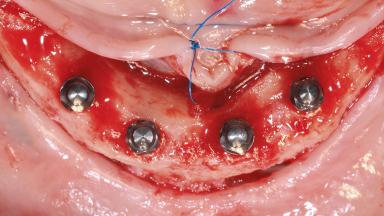

Immediate Loading of Four Narrow-Diameter One-Piece Implants in the Edentulous Mandible

A 63-year-old female patient presented at the School of Dental Medicine of the University of Bern, Switzerland (zmk Bern) with the goal of improving her dental appearance and finding relief from the persistent pain and discomfort in her teeth and gums. While recognizing the need for surgical interventions, she aimed to minimize the number of surgeries required. The patient suffered from obesity and mild hypertension, treated with amlodipine and valsartan under the care of her physician. She lived independently and appeared to be active and cognitively fit. Financial limitations for dental treatment were present.